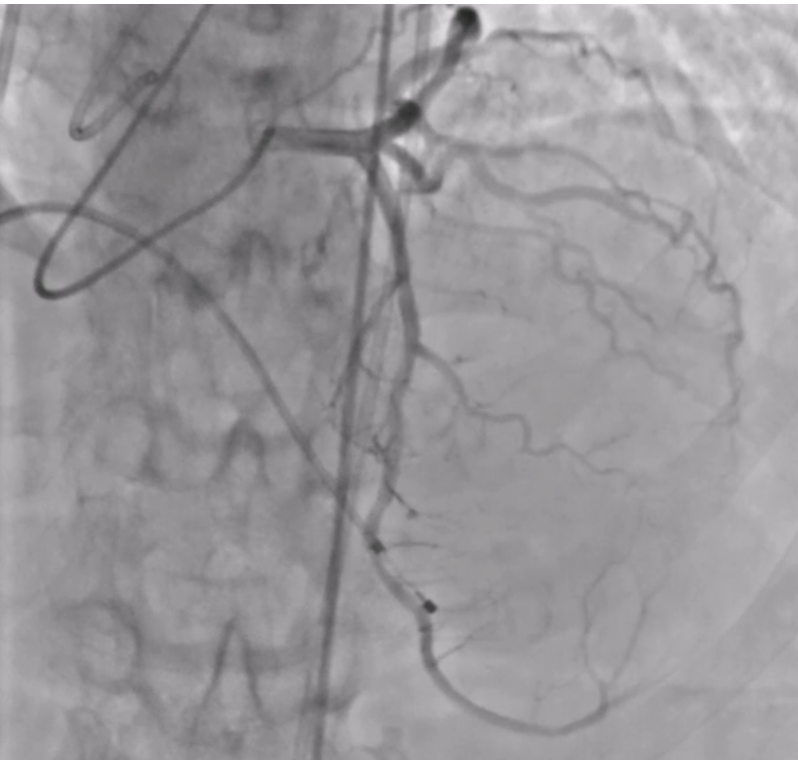

The patient was planned for transfemoral TAVI. Both left and right femoral arteries were punctured under ultrasound guidance. A temporary pacemaker (TPA) was placed in the right ventricle via the left femoral artery, and the right femoral artery sheath was upgraded to the 14Fr sheath. Selective left coronary angiography revealed normal coronaries. Through the right femoral artery, a snare was deployed in the abdominal aorta. The native bicuspid aortic valve was crossed with an Lunderquist wire, which was advanced into the left ventricle. Using pigtain, angiographic gradient was measured, showing severe aortic stenosis. Predilatation was performed using a 20 mm Z-MED balloon with satisfactory results. The TAVI valve, a self-expanding valve, was advanced across the native valve with the aid of the snare and positioned accurately in the cusp-overlap view. Under rapid pacing, the valve was deployed up to 80%, and after confirming satisfactory depth, full deployment was completed in the coplanar view. Final angiographic assessment showed no paravalvular leak (PVL) or aortic regurgitation (AR), with valve depth of 4–5 mm at the NCC and 6–7 mm at the LCC. Femoral closure was performed successfully without vascular complications.